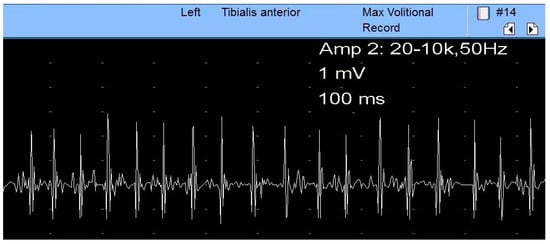

For SN assessment, NCS and EMG should be bilaterally conducted. The NCS studies of the fibular and tibial nerve, respectively, the fibular superficial nerve and sural nerve, are described in their chapters. The F responses of the tibial and fibular nerves and the H-reflexes are usually prolonged and should be studied. The fibular nerve is more severely affected than the tibial nerve and, where there is axonal loss, the CMAP amplitudes are reduced. The EMG study narrows the lesion site and quantifies the severity of the disease. The study protocol involves the examination of two fibular and tibial innervated muscles, the long and short heads of the biceps femoris muscle, and one muscle innervated by the superior and inferior gluteal nerves [28]. Thus, if muscles innervated by the fibular and tibial nerves and the biceps femoris muscle present EMG reduced recruitment of MUAPs, an SN lesion can be confirmed (Figure 7). Moreover, if an anomaly is found in the muscles innervated by the superior and inferior gluteal nerves, a plexopathy or radiculopathy is more likely. However, the L5 and S1 paraspinal muscles must also be assessed for the differential diagnosis between radiculopathy and plexopathy [28,48,54].

Figure 7.

Chronic neurogenic process in the muscle biceps femoris highlighted by neurogenic MUPs with high amplitude and poor interference pattern.